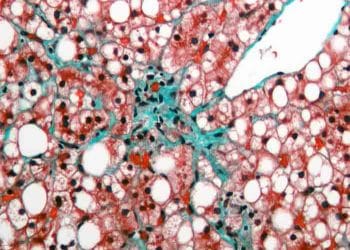

Kum kelebeği (Dicrocoelium dentriticum) koyun sürülerinin en büyük dertlerinden biridir. Dicrocoeliasis olarak bilinen bu hastalıkta kum kelebekleri karaciğer safra yollarına...